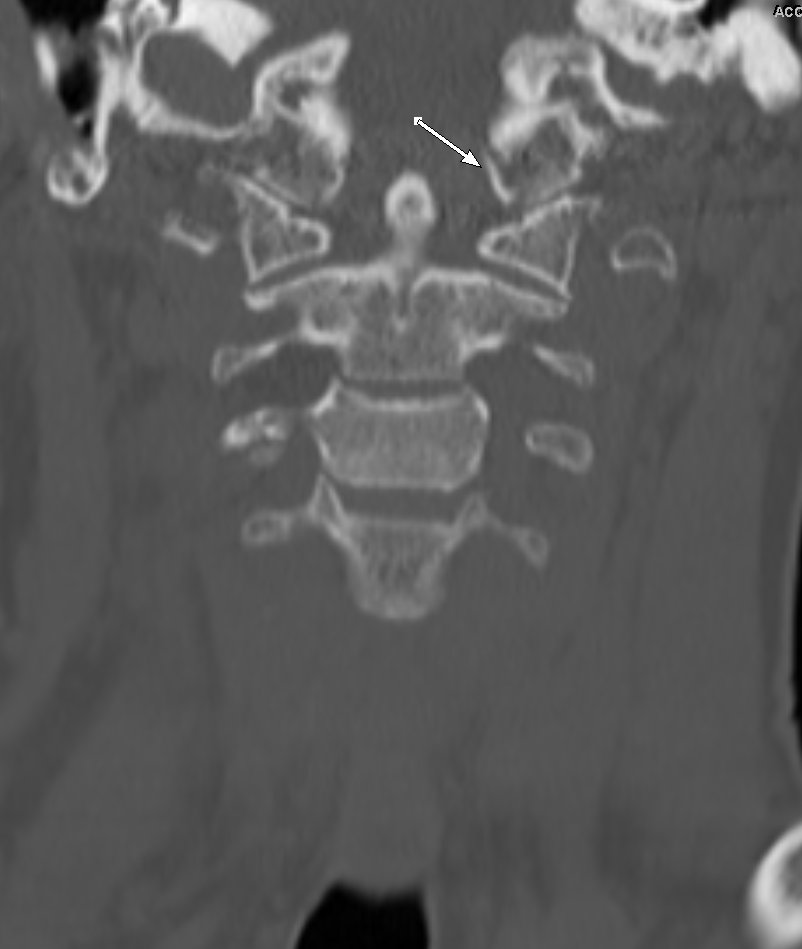

Occipital condyle avulsion fracture is often difficult to see on sagittal images

#radres always look on coronal and axial images, add this to your checklist#radiology#spine@NASSspine#EMRAd#FOAMed#spinetrauma#injurypic.twitter.com/lC7l73mnEj